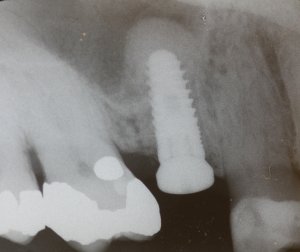

This seminar was presented by Dr. Stephen Wallace, Professor from Columbia University in New York. The focus of the course was a comparison between 2 surgical procedures for sinus elevation to increase bone thickness for dental implant stability in the upper posterior jaw. Comparisons were made between the newer systems of piezosurgery, an ultrasonic cutting device that utilizes piezoelectric vibrations in the application of cutting bone tissue. By adjusting the ultrasonic frequency of the device, it is possible to cut hard tissue while leaving soft tissue untouched by the process. The other system was the DASK System by Dentium which utilizes hydraulic pressure and diamond cutting surfaces which also readily cuts bone but not soft tissue. Both these procedures enhance the ease of the procedures and reduce the incidence of complications.